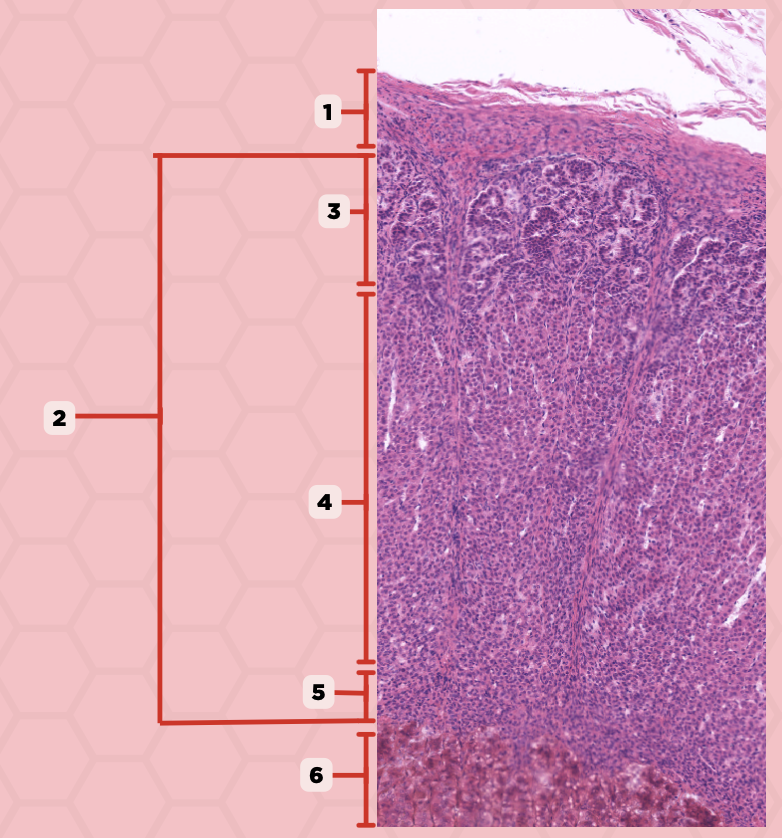

Adenohypophysis

What does #1, #4, and #5 form?

Pituitary

Identify the specimen.

Intermediate Lobe

Identify the structure labeled as 1.

Posterior Lobe

Identify the structure labeled as 2.

Pituitary Stalk

Identify the structure labeled as 3.

Pars Tuberalis

Identify the structure labeled as 4.

Anterior Lobe

Identify the structure labeled as 5.

Neural Ectoderm

What ectoderm is #2  derived from?

Oral Ectoderm

What ectoderm #1, #3, & #4 derived from?